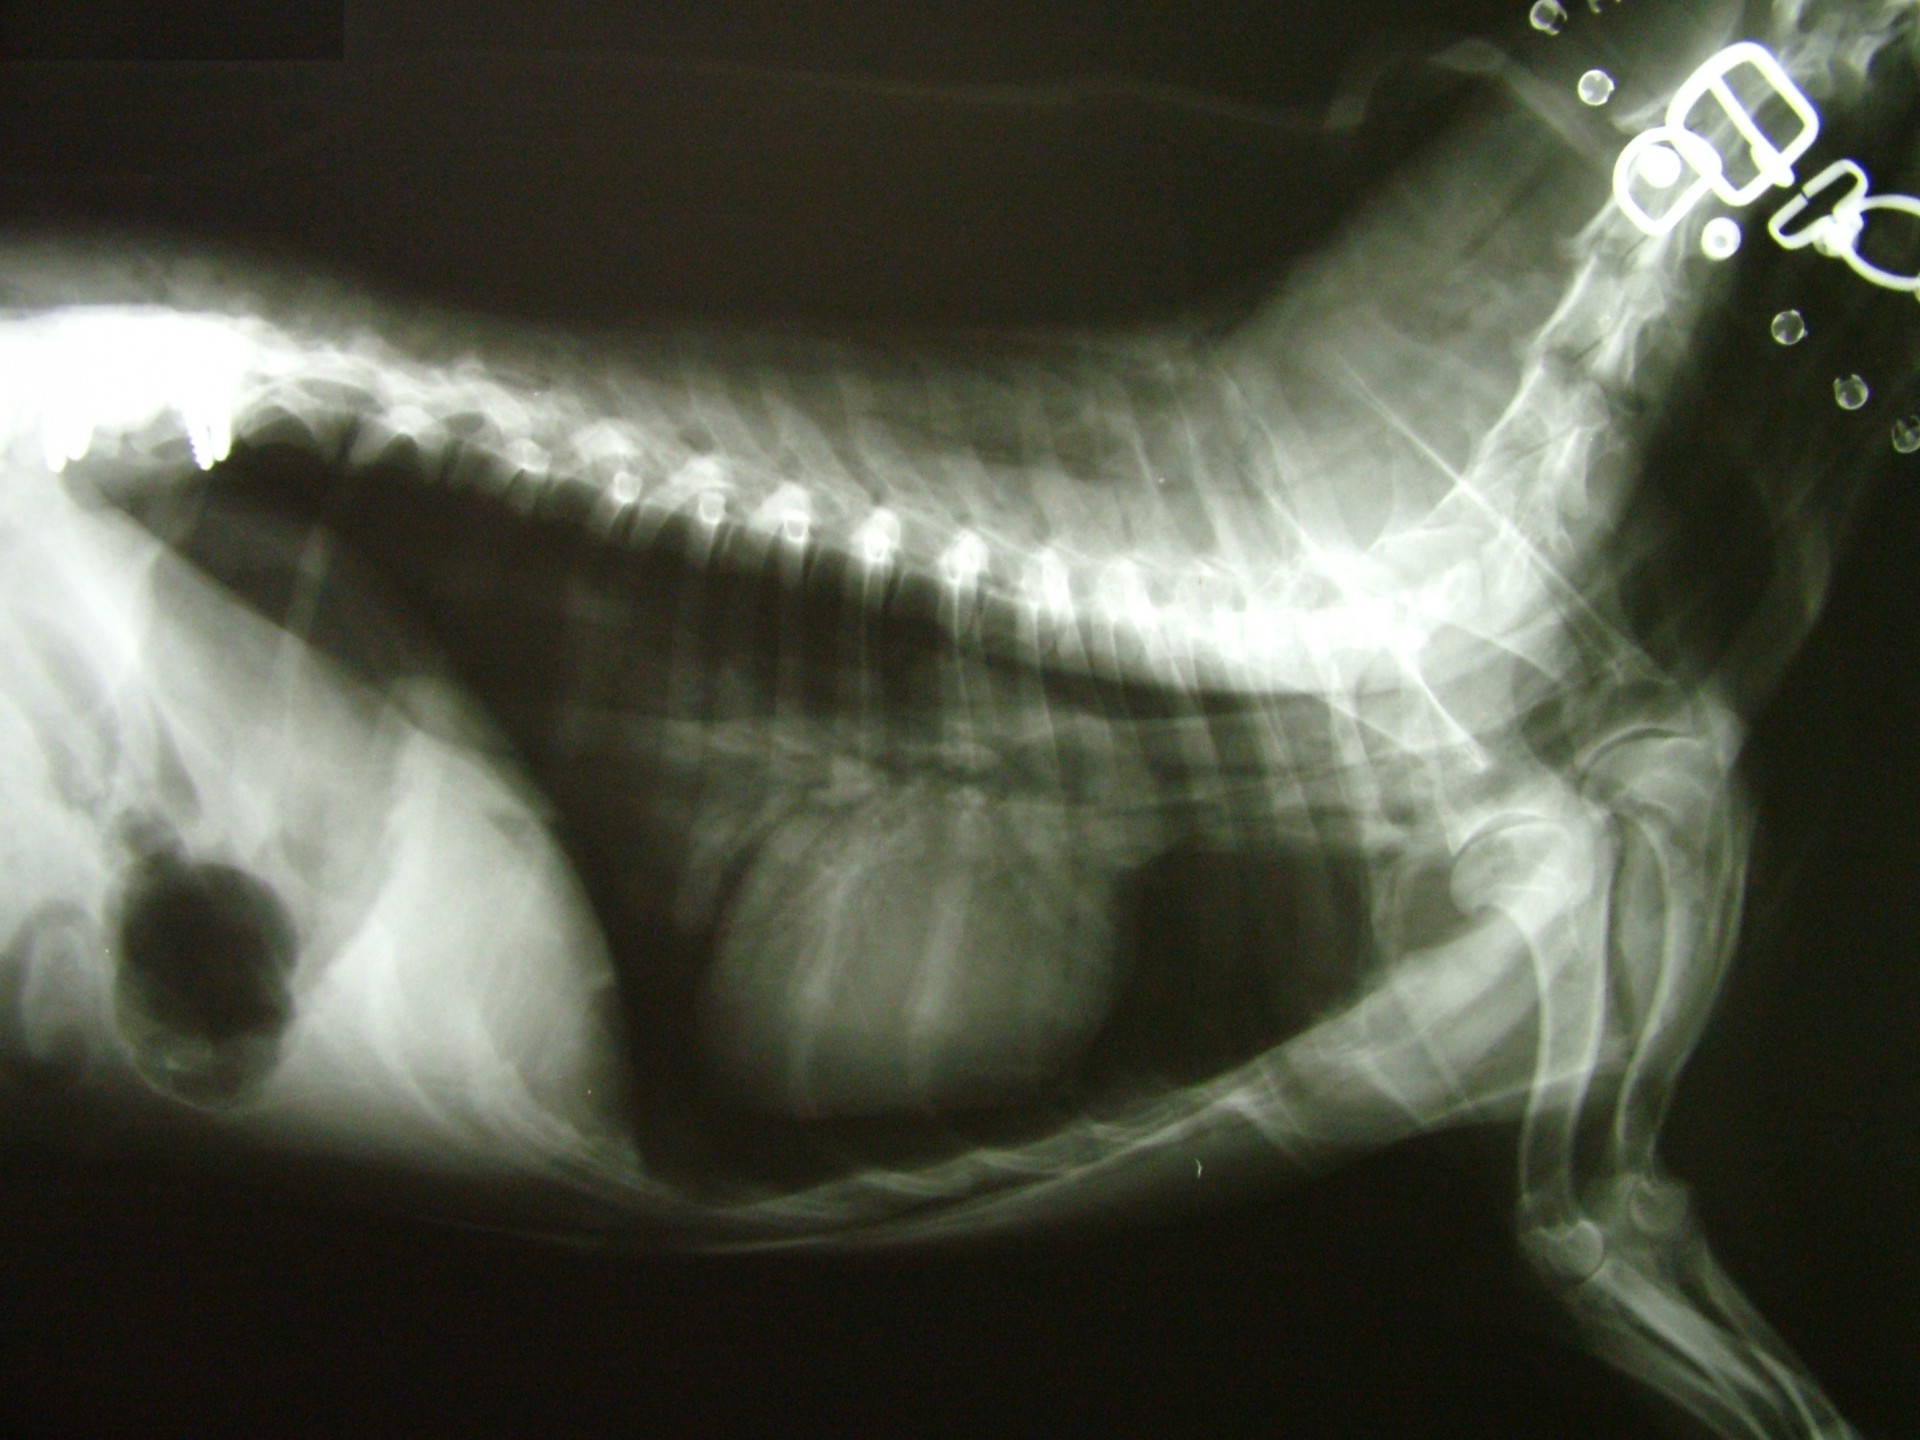

A gerinctörött állatok általában súlyos fokú hátsó testfél gyengeség tüneteit mutatják, a sérülés helyétől függően (a gerincoszlop mely szakaszán alakult ki gerincvelő sérülés) azonban a tünetek a mellső végtagokat is érinthetik. Ilyen tünetegyüttes a Schiff-Sherrington syndroma, melyben a gerincvelő sérülése mögötti területen petyhüdt bénulás, míg a sérülés előtti területen a nyújtó izmok fokozott tónusának megjelenése jellemző.

A gerincsérült állatokat ért traumás behatás természetesen nemcsak a gerincoszlopot, hanem egyéb szerveket is érhetik, ezért a gerincvelő sérülés ellátásához rendelkezésünkre álló idő (általában 24 óra) sok esetben az egyéb szervi sérülések miatt meglehetősen rövid vagy az egyéb sérülések következményei - egy akár sikeres gerincműtétet követően is - az állat halálát okozhatják. Ezért a balesetes állatok sérüléseinek ellátása fontossági sorrendben kell hogy megtörténjen, hisz eredményt csak akkor érhetünk el, ha az állat állapotát stabilizáljuk.

A gerinctörés diagnózisának felállítása komoly döntés elé állítja a tulajdonost és az állatorvost egyaránt. A gerinctörés következtében a gerincvelő minden esetben enyhébb-súlyosabb mértékben sérül. A gerincvelő sérülésének mértékét neurológiai vizsgálattal állapítjuk meg, de a diagnózis felállításához nélkülözhetetlen röntgen felvételről is már információt nyerhetünk a gerincvelő várható állapotáról. A tört végek egymáshoz képest történő kis mértékű elmozdulása esetén a gerincvelő körüli területek bevérzése miatt kialakult neurológiai tünetekkel találkozunk míg nagymértékű elmozdulásuk a gerincvelőt gyakorlatilag olló szerűen elnyírhatja. Így a natív röntgen felvételen a gerinccsatorna elmozdulásából már következtetést vonhatunk le a gerincvelőt ért sérülés mértékéről. A gerincvelő tényleges állapotáról azonban csak neurológiai vizsgálattal győződhetünk meg!